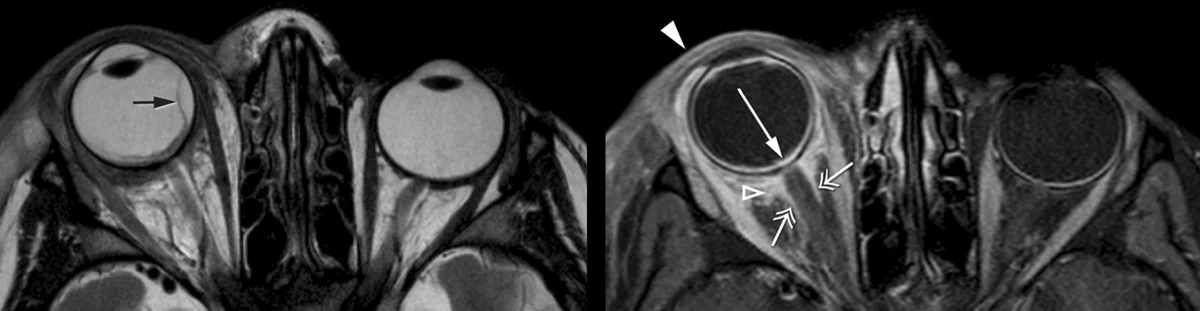

Other Ocular Imaging Applications

In addition to our ocular MRI research, we explore the application of our methods for other body parts and assist in various other projects within the Gorter Center.

These projects include the studying the pathophysiology of the extra-ocular muscles in Myasthenia Gravis patients, improving the quantification of MRI-sequences and improving the calibration of ophthalmic instrumentation.